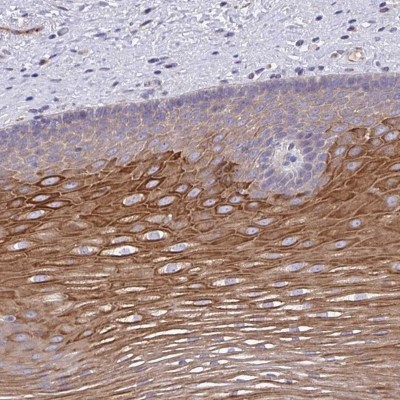

- Immunohistochemistry-Paraffin: OR10Z1 Antibody [NBP2-33991] - Staining of human esophagus shows strong cytoplasmic positivity in squamous epithelial cells.